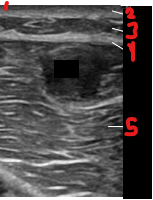

Identify this image.

Layers of skin

Epidermis

Dermis

Hypodermis or subcutaneous adipose tissue

Fascia

Muscle